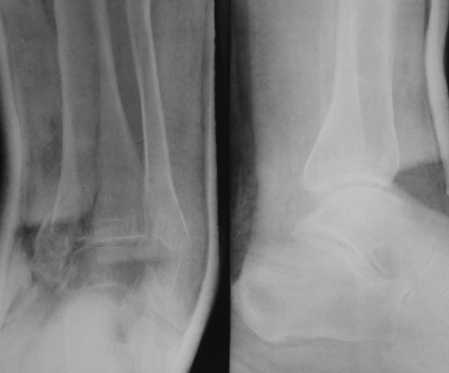

Уважаемые коллеги! Обратилась больная 62-х лет.

Перелом в быту - запнулась о порог в комнате, подвернула стопу. Рекомендуем первичный артродез. Хотелось бы услышать мнения по тактике лечения и способу фиксации.